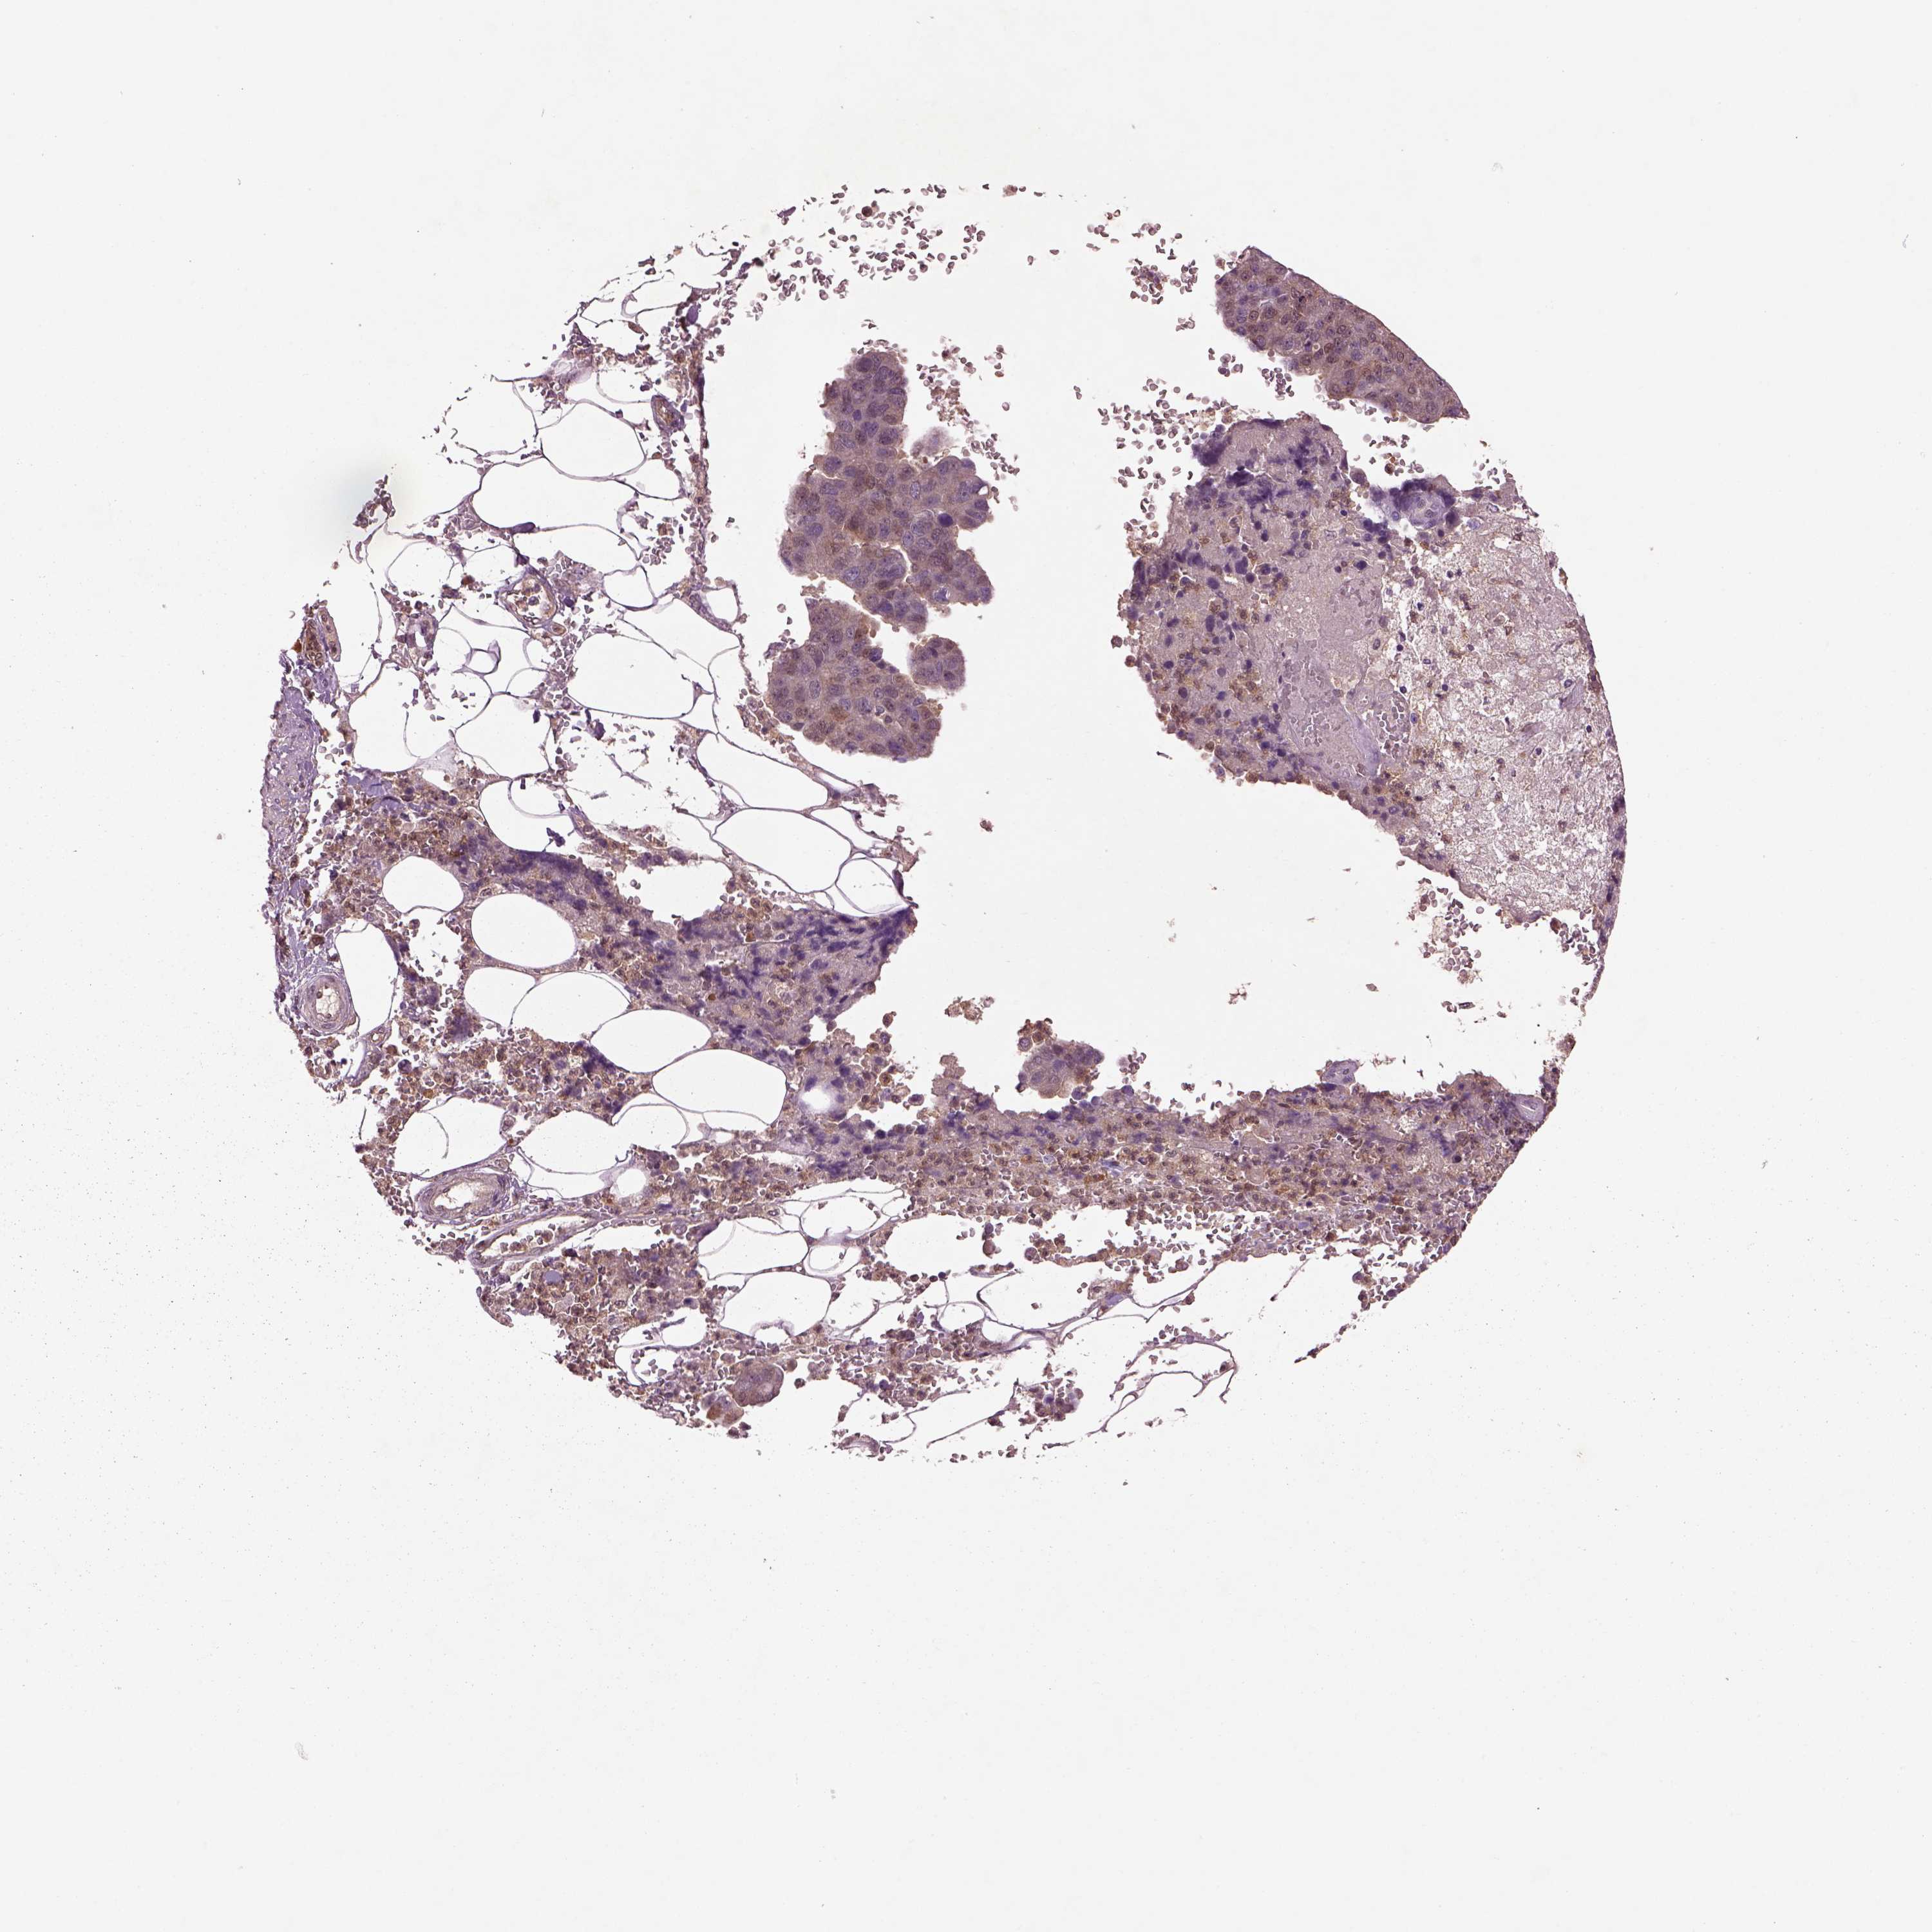

PANCREATIC CANCER - Protein expressioni

A mouse-over function shows sample information and annotation data. Click on an image to view it in a full screen mode. Samples can be filtered based on level of antibody staining by selecting one or several of the following categories: high, medium, low and not detected. The assay and annotation is described here.

Note that samples used for immunohistochemistry by the Human Protein Atlas do not correspond to samples in the TCGA dataset.

Antibody stainingi

Antibody staining in the annotated cell types in the current human tissue is reported as not detected, low, medium, or high, based on conventional immunohistochemistry profiling in selected tissues. This score is based on the combination of the staining intensity and fraction of stained cells.

Each image is clickable and will lead to virtual microscopy that enables deeper exploration of all samples and also displays staining intensity scores, fraction scores and subcellular localization as well as patient and tissue information for each sample.

Antibody HPA003064

Antibody HPA070338

Adenocarcinoma, NOS